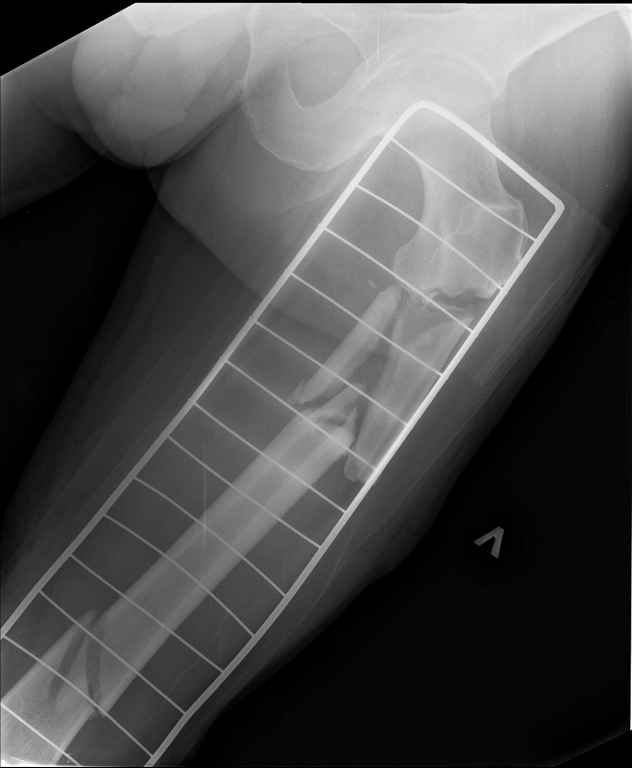

Ds: ТСТ. ЗЧМТ. СГМ. ЗТГК. О/фрагментарный перелом левого бедра. З/оскольчатый перелом с\3 левого плеча. Перелом левого локтевого отростка. З/перелом наружного мыщелка б/берцовой кости в/3 м/берцовой кости левой голени. при поступлении, ПХО раны левого бедра( рана 1х1см по наружной поверхности бедра в с/3) налажено скелетное вытяжение , и гипсовая лонгета на левую в/конечность. Находился в реанимации. 17.02.11 был прооперирован: БИОС левого плеча, о/синтез левого локтевого отростка по Веберу, БИОС левого бедра (длинная версия Fi-Can Sanatmetal диаметр 10мм), мыщелок голени трогать не стали.при остеосинтезе бедра возникли трудности при закрытй репозиции перелома в н/3, в связи с чем решили открыться внизу , отрепонировали без особого труда и выполнили блокирование во фронтальной плоскости 3-мя винтами + 1 винт спереди гвоздя (промазал). Убрал костодержатель, все нормально, контроль ЭОПом стояние отломков нормальное, зашились. На контрольной R-мме на утро выявлено вторичное смещение дистального отломка. Левая нога по сравнению со здоровой удлиннена до 2,5см( это за счет вальгусной установки гвоздя в проксимальном отделе, боялся свалиться на варус). Теперь думаем как поправить положение отломков в н/3, и зафиксировать так чтобы не съехало. Наше предложение расшиться в н/3 бедра, разблокироваться, перелом отрепонировать вновь и установить 1или 2отклоняющих винта в сагитальной плоскости, затем заблокироваться во фронтальной плоскости снова. Помогите советом, как выйти достойно из сложившейся ситуации. Заранее спасибо.

Если возникло вторичное смещение, то - наверняка получится закрытая повторная репозиция дистального фрагмента,затем отклоняющие винты (ввиду отсутствия отверстий в сагиттальной плоскости).

Высказывались предложения разблокировать, растянуть, попытаться исправить угол, не вынимая гвоздя и не раскрываясь. Не важно чем будете (если будете) это осуществлять, дистрактром или на орт.столе. Думается, что на столе удобнее - сроки позволят. Если дистрактором - спицу(стержень) дистальной опоры проводить учетом коррекции того самого вальгуса до начала дистракции. На счет возникшего смещения можно сказать что оно могло случиться и после блокирования - оси винтов как раз назодятся в плоскости смещения. Доселе Вы читали доклад на симпозуиме АО про дистальное плечо, про то как не подходят БИОС конструкции для тех переломов, так вот при широком канале адекватно гвоздь будет удерживать отломки от варусно- вальгусного смещения, если блокирующий винт пройдет в сагитальной плоскости. Не важно дистальное ли это плечо голень или бедро, как в Вашем случае. Т.е. если удастся исправить деформацию в дистальном бедре сагитальное запирание будет не лишним.